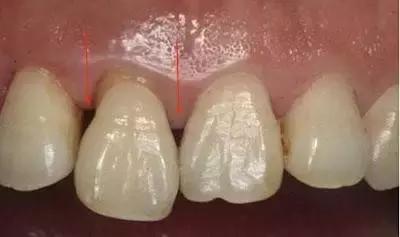

如果两颗牙齿之间的牙龈乳头退缩(牙龈萎缩),就会造成两颗牙齿之间下方出现空隙,食物就比较容易在嘴唇、脸颊和舌头的运动作用下,水平地进入了间隙,造成了“卡肉”的现象。

牙龈萎缩,需要考虑系统的牙周治疗或手术。